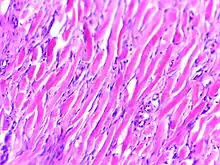

Histologically, keloids are fibrotic tumors characterized by a collection of atypical fibroblasts with excessive deposition of extracellular matrix components, especially collagen, fibronectin, elastin, and proteoglycans. Generally, they contain relatively acellular centers and thick, abundant collagen bundles that form nodules in the deep dermal portion of the lesion. Keloids present a therapeutic challenge that must be addressed, as these lesions can cause significant pain, pruritus (itching), and physical disfigurement. They may not improve in appearance over time and can limit mobility if located over a joint.[11]